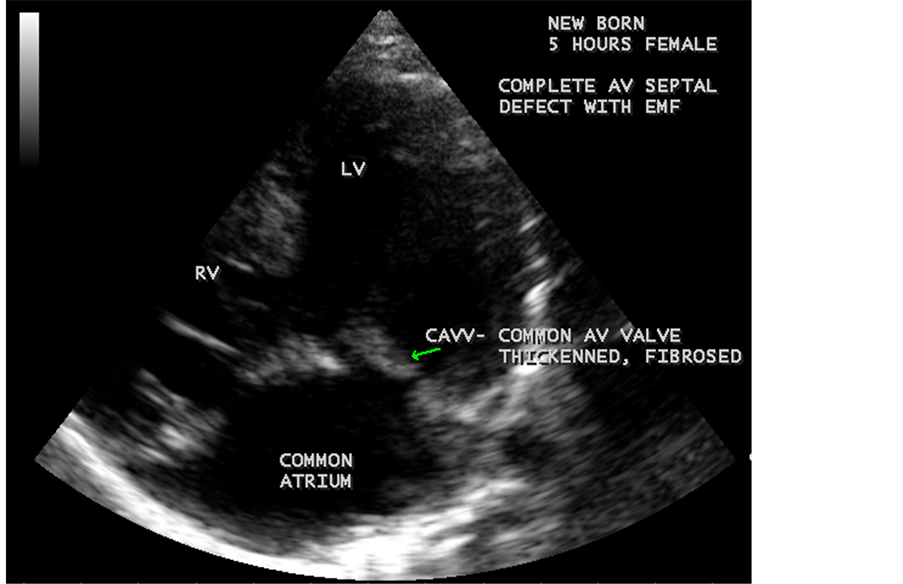

Figure 68. Showing the complete AV septal defect with fibrosis of CAVV (common AV valve) in a new born with EMF.

Figure 69. Showing the common AV (atrioventricular) valve which is thickenned and fibrosed in a newborn with EMF (endomyocardial fibrosis).

Figure 70. Showing the calcification of CAVV (common AV valve) and endocardial calcification of left ventricle in complete AV septal defect with EMF in new born.

Figure 71. Showing the subvalvular fibrosis of the CAVV (common AV valve) in EMF.

Figure 72. Showing the CAVV (common AV valve) regurgitation in new born.

RV EMF was detected antenatally in a 22-year-old woman with 8 months amenorrhea as in Figure 67. Endomyocardial fibrosis with left ventricular endocardial calcification and subvalvular fibrosis was detected in a new born with complete AV (atrioventricular) septal defect as shown in Figure 68 to Figure 72. EMF associated with fibrosis of papillary muscle and aneurysmal left ventricle is shown in Figure 74 and Figure 75 in a 56-year-old female. RV EMF associated with right sided pleural effusion, massive ascites and smoke (spontaneous echo contrast) in both ventricles are shown in Figure 76 to Figure 82 in a 42-year-old male. Classical case of RV EMF was shown in Figure 83 and Figure 84 in a 55-year-old male.